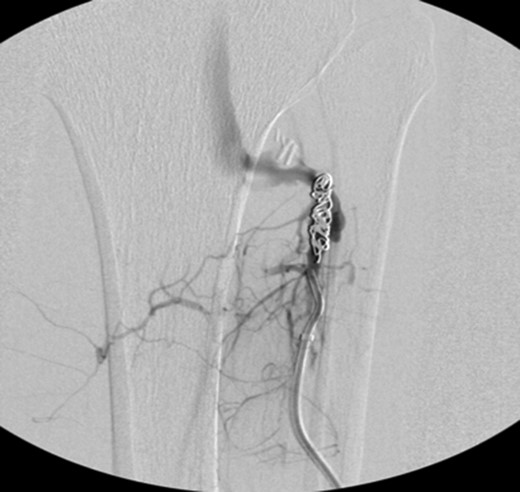

Patient underwent a left lower extremity angiogram. During the procedure she was found to have patent aorta and bilateral common iliac artery. There was no disease visualized in the left external iliac artery, common femoral artery (CFA), SFA, patent previously placed stent, patent above and below the knee PA and two vessel run off to the foot (Fig. 1). Upon delayed fluoroscopic images we identified contrast filling the deep venous system rather quickly suggesting a high volume fistula (Fig. 2). We then identified the fistula between ATA and ATV. Although ATA was previously ligated there was retrograde filling of the artery from unnamed branches, which communicated with the venous system as shown in. In the midcalf (ATA) was cannulated with a micropuncture needle. Micropuncture wire was inserted and a 5-Fr sheath was inserted after exchanging over wire. At this point VortX coils (Boston Scientific) were placed from the curve of ATA until the whole AVF was sealed. Anterograde angiogram showed no flow through the fistula (Figs 3 and 4). There was a palpable PT and DP pulse at the completion of the procedure. Sheath was removed, pressure dressing applied. Patient was discharged home same day. Recovery has been unremarkable. Three months follow-up claudication symptoms have significantly improved.

VortX coils (Boston Scientific) were placed from the curve of anterior tibial artery to its communication with venous system.